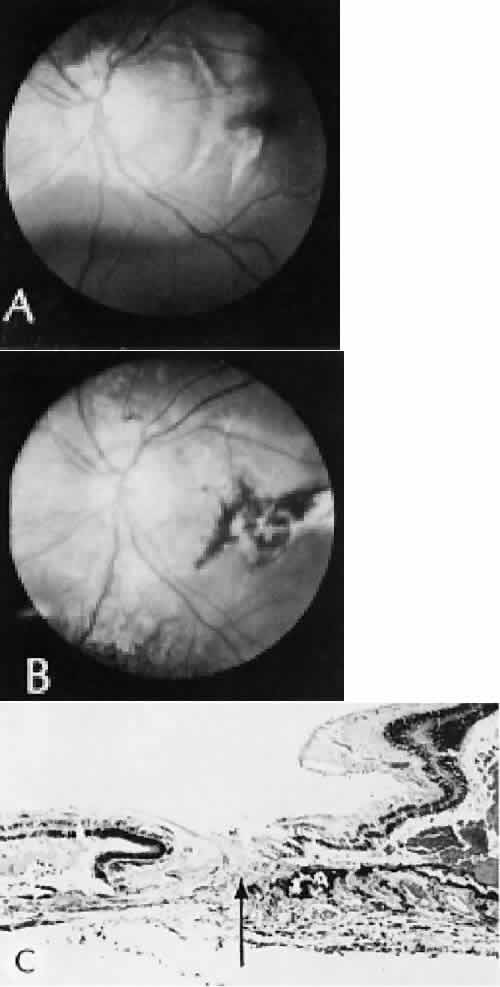

RETINAL HEALING

Wound healing of the neurosensory retina follows the principles of wound healing. There is an initial removal of all necrotic tissue by phagocytosis followed by proliferation of cells to form a chorioretinal bond. The healing, however, is modified in most instances by the lack of participation by the blood vessels.43–45 Astrocytes from the neurosensory retinaproliferate from the peripheral viable tissue into the wound and downward into the area of the subretinal space (Fig. 12). Retinal pigment epithelial cells from the peripheral viable tissue undergo fibrous metaplasia and proliferate upward into the area of the subretinal space. When the two proliferating cell types unite, a tight chorioretinal bond is formed. Increased retinal adhesiveness has been estimated to be 140% of the normal degree of adhesiveness 2 weeks after photocoagulation.46 Retinal holes may heal spontaneously if supported by an intact vitreous base or if located adjacent to the retinal pigment epithelium (Fig. 13).47,48 For the retinal pigment epithelium to differentiate, it must be in contact with overlying retinal pigment epithelium.49 Choriocapillaris repair from a photocoagulation wound of the retina appears to proceed in a manner similar to that of repair of capillary thrombosis in other tissues.50 The vascular repair process may not reproduce the lobular architecture of the native choriocapillaris.51 The choriocapillaris may regenerate in areas of restored retinal pigment epithelium.52 Proliferative vitreoretinopathy is an expression of abnormal retinal wound healing.53

Fig. 12. Light micrograph of an area over a retinal buckling element for retinal reattachment. Cryotherapy has been applied in the area, causing atrophy of the neurosensory elements of the retina. There is an intimate association of the remaining glial elements of the retina (R) with proliferated retinal pigment epithelial cells in the plane of the former subretinal space (arrow). The adhesion prevents intraretinal separation in this area. (Periodic acid-Schiff stain; × 100.)